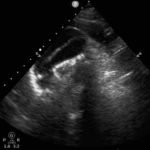

We present a case of a 51-year-old previously healthy man who presented to the ED complaining of chest pain that had resolved prior to arrival, and a mild headache. His vital signs were notable for hypotension, but physical exam was unremarkable. Chest x-ray revealed a borderline widened mediastinum. A standard ETTE was within normal limits, but additional SSNV demonstrated a dissection flap in the aortic arch. The patient was taken to the operating room for surgical repair 75 minutes after the ED ultrasound was performed; the operation was successful, and the patient was discharged to home post-operatively with good outcome.

Standard ETTE has limited ability to visualize the ascending aorta and aortic arch. Addition of SSNV allows visualization of these structures and may improve diagnostic accuracy and time to diagnosis of proximal aortic dissection.